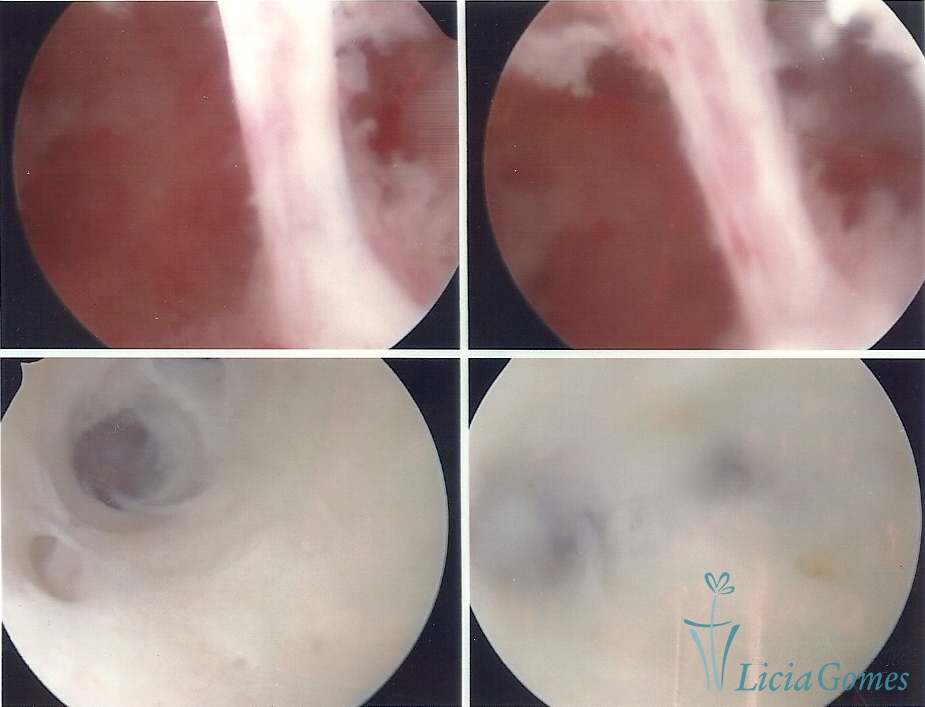

FIBROUS SYNECHIA

• SINÉQUIA TIPO FIBROSA